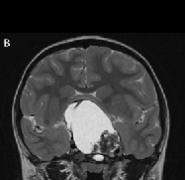

儿童颅咽管瘤是一种少见的、鞍区或鞍旁区胚胎性畸形的低级别组织学恶性肿瘤。由于颅咽管瘤与视交叉、脑垂体和下丘脑在解剖学上的邻近关系,其不良...

儿童期颅咽管瘤 是少见的,蝶鞍或鞍旁区域的胚胎发生畸形,伴有低度组织学恶性肿瘤。颅咽管瘤由于接近视交叉,脑垂体,经常影响儿童的生活质量(...

颅咽管瘤是由鞍区或鞍上区Rathke囊的残余细胞形成的肿瘤,具有囊性和实型成分。虽然它们是良性的,WHO为I级,但由于该病难以治愈,使得它们的生长行为...